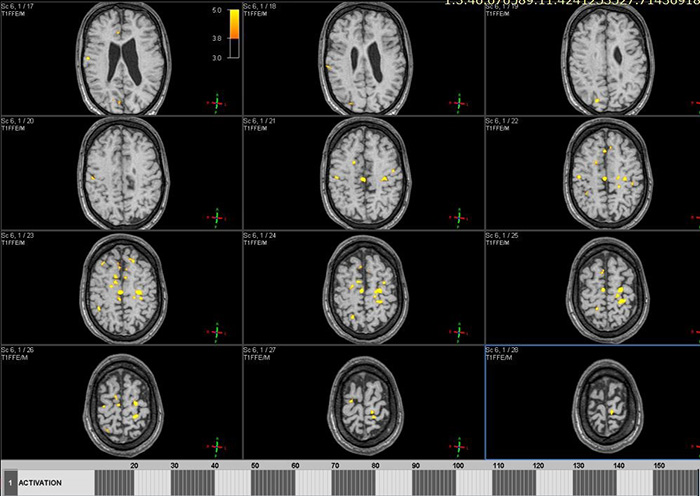

Цель: Апробация и внедрение в клиническую практику современных методик фМРТ и DTI для оценки структурных и функциональных изменений при нарушениях движения у детей. Описание проекта: Для Детского Церебрального Паралича характерно наличие незначительных структурных повреждений [1], при этом неясна их связь с нарушениями двигательных функций. фМРТ позволяет выявить зоны активации мозга при выполнении движений и оценить сложность выполнения задания по объему зон активации (Рис 1). МР-трактография позволяет исследовать структуру и диффузионные характеристики проводящих путей мозга (Рис 2). МР-волюметрия также позволяет оценить объем основных структур мозга и выявить аномалии развития, кортикальные дисплазии и патологии белого вещества мозга (Рис 3.). Результаты: Проведена клиническая апробация предложенных методик. Результаты представлены на медицинских неврологических конгрессах.

Рис. 3. МРТ данные пациента с ДЦП: на FLAIR изображениях структурные изменения минимальны.